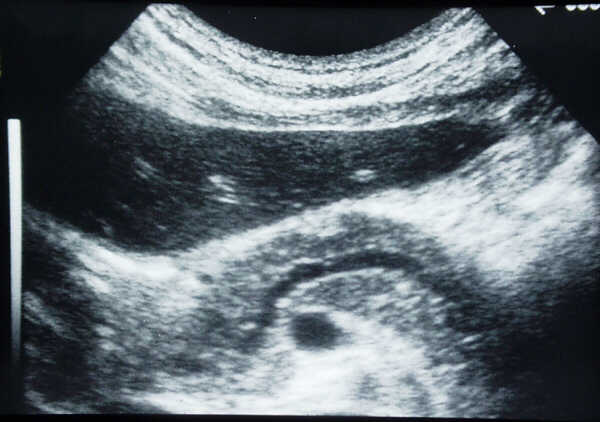

Transverse

scan in a patient with a little cancer in the pancreatic head. The tumor is not

detectable but the dilated Wirsung duct is well

visualized.